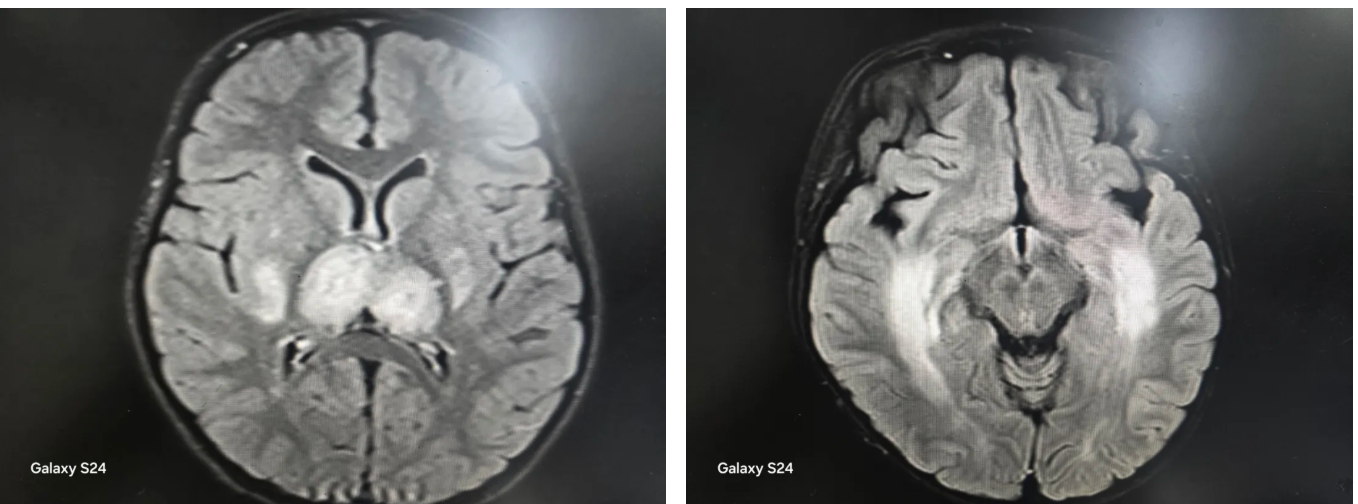

“前几天我们接诊了一名6岁女童,从咳嗽发热到抽搐昏迷,仅仅用了一天时间。”龙梅主任回忆道,孩子送来时已处于昏迷状态,面色苍白,经过紧急检查,最终确诊为“儿童急性坏死性脑病”——一种由流感引发的罕见却极其凶险的中枢神经系统并发症。

急性坏死性脑病主要发生在婴幼儿和儿童群体,多由甲型流感病毒感染诱发。它的可怕之处在于,发病机制并非病毒直接侵袭大脑,而是病毒感染后触发人体过度、失控的免疫反应。

“我们称之为‘炎症风暴’。”龙梅主任用形象的比喻描述,“就像身体的免疫系统突然‘暴动’,原本应该保护机体的免疫细胞开始疯狂攻击自身组织,特别是脑部血管和神经细胞,导致大脑多部位发生对称性坏死。”